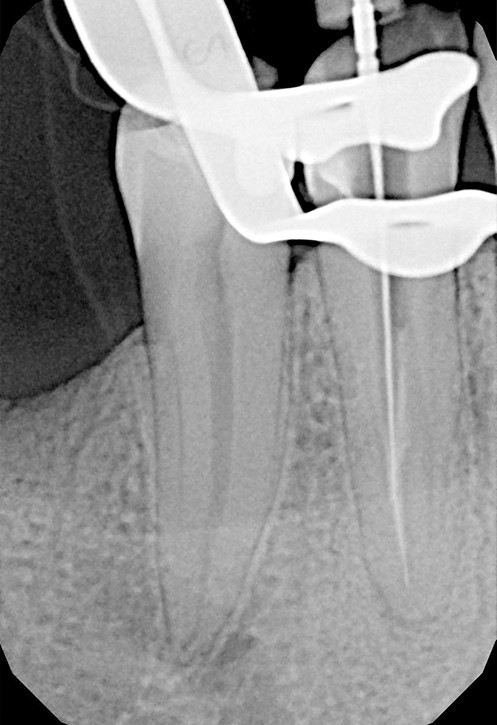

Stożkowa tomografia komputerowa CBCT, ze względu na dokładne, trójwymiarowe obrazowanie 3D, bez zniekształceń ukazuje szczegóły anatomii zęba oraz okolicznych tkanek, wyjaśniając nierzadko problemy niemożliwe do zdiagnozowania standardowymi metodami.

Na podstawie zdjęcia rentgenowskiego określa się kształt i długość kanału bądź za pomocą specjalnego urządzenia mierzy się jego długość. Potem lekarz otwiera wejścia do kanału, chroniąc ząb koferdamem, czyli specjalną gumą, zapewniającą sterylność oraz chroniącą przed środkami chemicznymi służącymi do oczyszczania kanału. Używa się do tego zarówno specjalistycznego sprzętu, jak i nowoczesnych mikroskopów, pozwalających na uzyskanie dokładnego obrazu leczonego zęba. Ostatnią czynnością jest wypełnienie materiałem światłoutwardzalnym i zabezpieczenie zęba przed dostaniem się i rozwojem bakterii mogących wywołać wtórny stan zapalny.

LECZENIE ENDODONTYCZNE ZE SKOMPLIKOWANĄ ANATOMIĄ ZĘBA

Leczenie kanałowe zęba pod mikroskopem daje lepszy wgląd w pole zabiegowe podczas odnajdywania i udrażniania kanałów korzeniowych oraz ich poszerzania i precyzyjnego wypełniania. Powiększony obraz ułatwia i przyspiesza pracę szczególnie przy niestandardowej anatomii zęba.

Leczenie pod mikroskopem nie różni się znacząco od standardowych technik. Pacjent zawsze pozostaje w pozycji leżącej i jest zaopatrzony koferdamem. Koferdam to gumowa ochrona zabezpieczająca pacjenta przed połykaniem drażniących płynów dezynfekujących kanały korzeniowe. Chroni również kanał korzeniowy przed wtórnym infekowaniem ich śliną. Powiększony obraz uzyskany w optyce mikroskopu poprawia precyzję i przyspiesza pracę endodoncie.